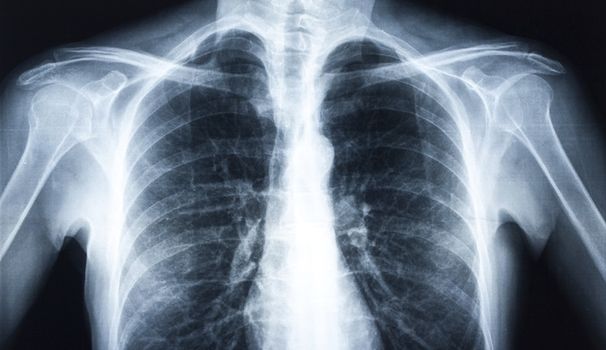

Hundreds of patients recalled after X-ray errors

Hundreds of patients have been recalled to Irish hospitals after errors were discovered in X-ray readings taken by three locum radiologists.

The mistakes have reportedly led to a late cancer diagnosis in one case and thousands of scans had to be reexamined after colleagues raised concerns about the quality of the work to the Health Service Executive.

Almost 4,500 scans and X-rays taken between May and September 2013 had to be rechecked in Bantry, where 50 patients were recalled. A further 62 patients were asked to return to the hospital in Cavan, while six more were recalled in Kerry.